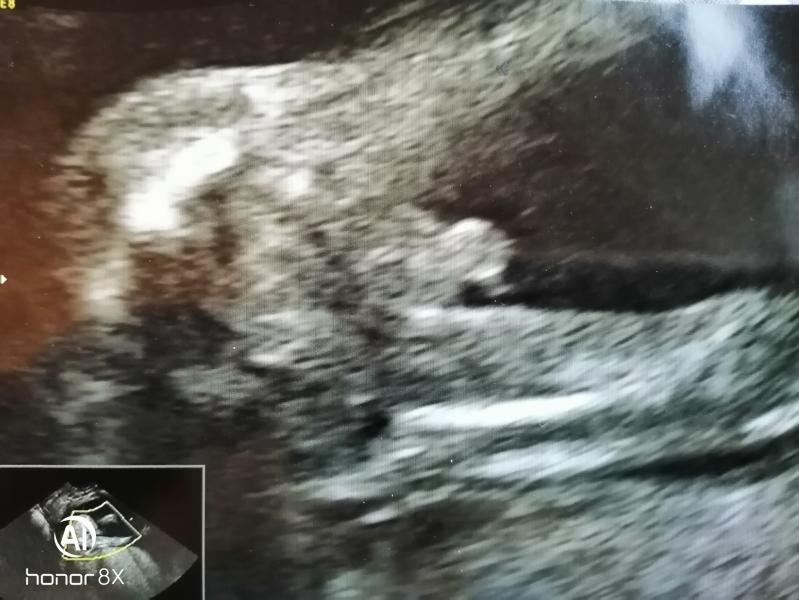

Ух узнали с мужем сегодня что у нас будет мальчик. Уррра.